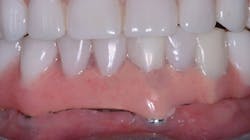

Speech challenges—Often, edentulous patients with fixed prostheses complain of lisping or a whistle sound due to spaces underneath the prosthesis (figure 5). This condition is most common when the implants have been placed and not allowed to mature, causing soft-tissue shrinkage that occurs as subsequent healing occurs.

Figure 5: The space under the fixed prosthesis produced an objectionable hiss and lisp as the patient spoke.